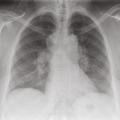

La radiographie thoracique est essentielle au diagnostic et pour le suivi de la maladie, elle est anormale dans 90 à 95 % des cas.32 Certains signes sont typiques et présents dans 50 à 80 % des cas : les adénopathies hilaires bilatérales symétriques et non compressives (fig. 1). La présence d’adénopathies médiastinales, sans atteinte hilaire ou unilatérale, est très atypique et doit faire rechercher un diagnostic différentiel (cancer, hémopathie, tuberculose). L’infiltration parenchymateuse, si elle est présente, prédomine dans les territoires supérieurs et moyens. La classification de Scadding distingue 5 stades corrélés avec la probabilité de guérison spontanée de la sarcoïdose :

– stade 0 : radiographie normale au cours d’une sarcoïdose extrathoracique ;

– stade I : stade le plus fréquent, caractérisé par des adénopathies sans atteinte parenchymateuse ;

– stade II : adénopathies associées à une atteinte parenchymateuse ;

– stade III : atteinte parenchymateuse isolée sans fibrose ;

– stade IV : fibrose pulmonaire.

La probabilité de guérison est respectivement de 60-90 %, 40-70 %, 10-20 % et 0 % pour les stades I, II, III et IV.